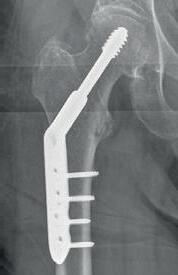

Hvis man vælger osteosyntese, er der overordnet to valgmuligheder:

1. Skrueosteosyntese, som kun bør bruges til de subcapitale frakturer og udislocerede frakturer

2, Glideskrue (Dynamic Hip Screw = DHS), som bør være førstevalg til transcervikale og basocervikale frakturer, da den øgede stabilitet i implantatet ift. skruer giver en lavere reoperationsprocent.

Valget af implantat bør altså samlet set afhænge af alder, funktionsniveau og komorbiditet, og der bør i tvivlstilfælde være en grundig snak med patienten før operationen for at afklare valget. Her er to cases

med en disloceret collum femorisfraktur for at illustrere dette: En 52-årig mand, plejehjemsbeboer med demens og dårlig gangfunktion, bør nok have en hemialloplastik, mens en 72-årig kvinde, som cykler 50 km ugentligt og spiller golf tre gange om ugen, godt kan tilbydes valget mellem osteosyntese og en alloplastik.

Den grove opdeling i implantatvalg ses i tabel 21.2. Se desuden den samlede behandlingsalgoritme i tabel 21.4.

* DHS = Dynamic Hip Screw **Aldersgrænsen er vejledende, og der kan tages højde for patientens funktionsniveau og komorbiditet.